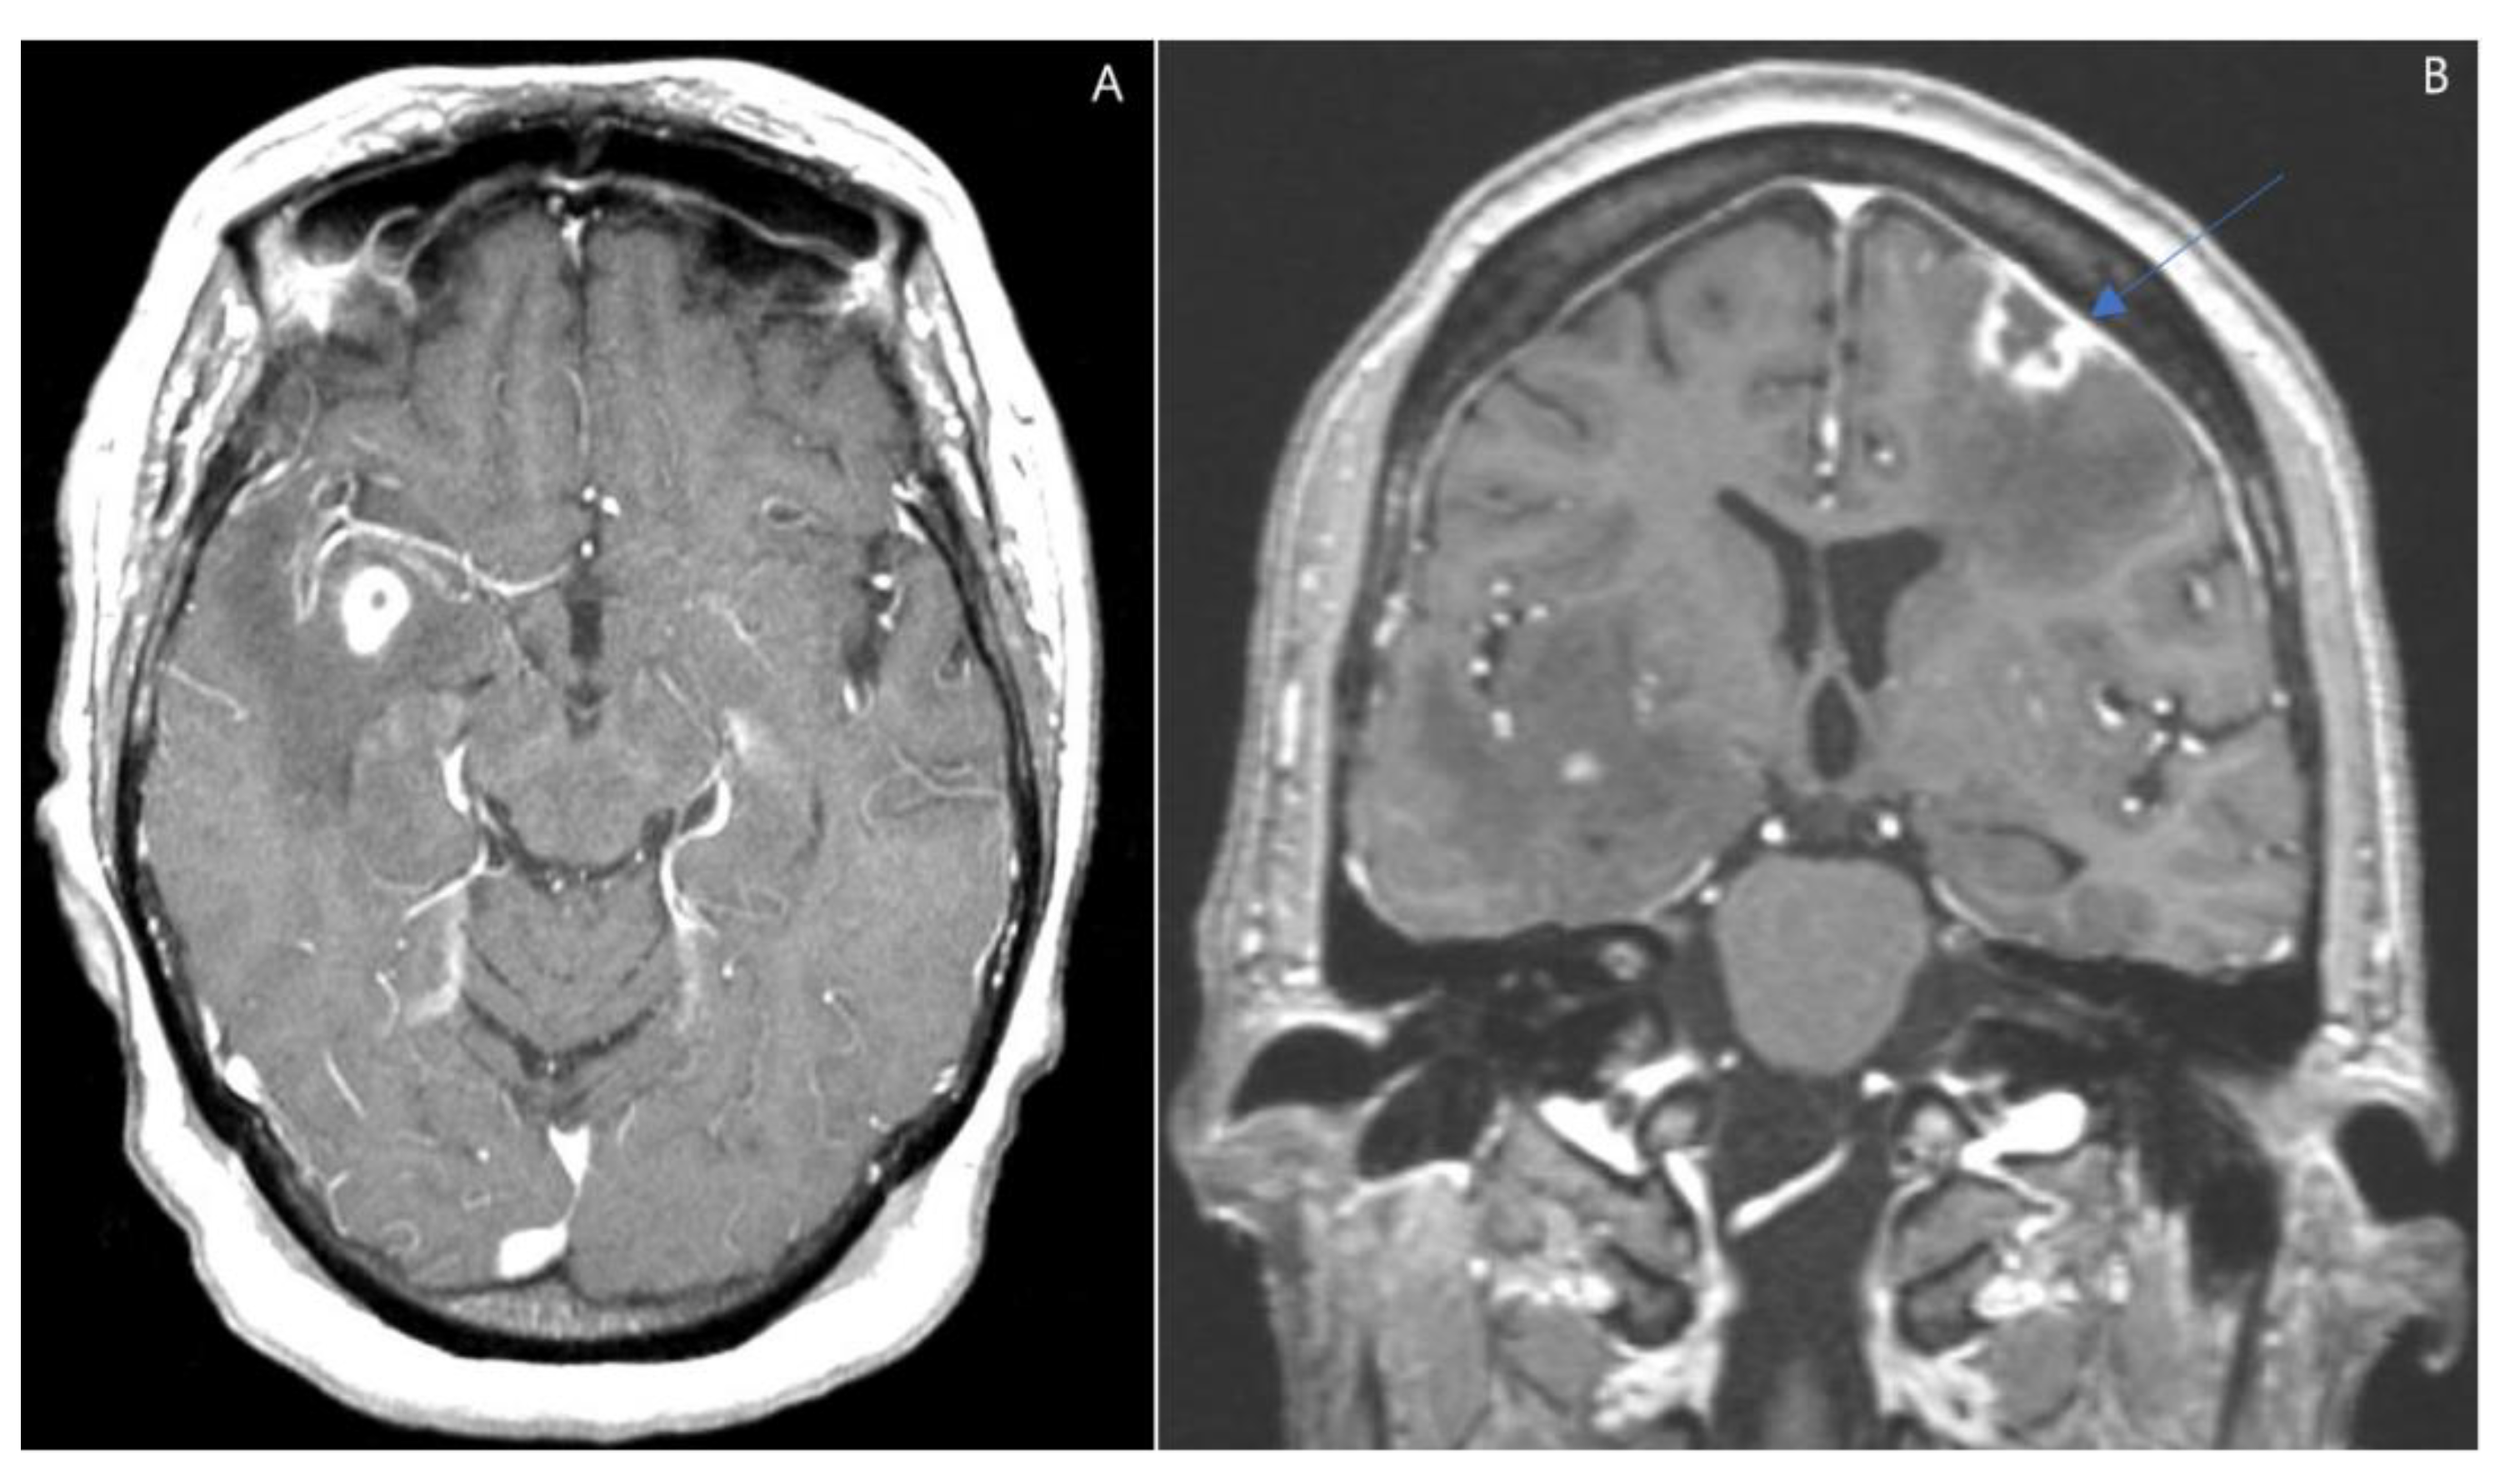

2. Case Presentation